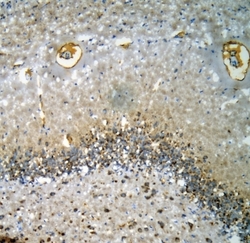

R31325 IHC

Full details

Method:

Other validation